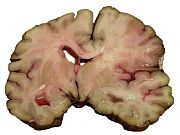

Hemorrhagic stroke

Intracranial hemorrhage is the accumulation of blood anywhere within the skull vault. A distinction is made between intra-axial hemorrhage (blood inside the brain) and extra-axial hemorrhage (blood inside the skull but outside the brain). Intra-axial hemorrhage is due to intraparenchymal hemorrhage or intraventricular hemorrhage (blood in the ventricular system). The main types of extra-axial hemorrhage are epidural hematoma (bleeding between the dura mater and the skull), subdural hematoma (in the subdural space) and subarachnoid hemorrhage (between the arachnoid mater and pia mater). Most of the hemorrhagic stroke syndromes have specific symptoms (e.g. headache, previous head injury).

Intracerebral hemorrhage (ICH) is bleeding directly into the brain tissue, forming a gradually enlarging hematoma (pooling of blood). It generally occurs in small arteries or arterioles and is commonly due to hypertension, trauma, bleeding disorders, amyloid angiopathy, illicit drug use (e.g. amphetamines or cocaine), and vascular malformations. The hematoma enlarges until pressure from surrounding tissue limits its growth, or until it decompresses by emptying into the ventricular system, CSF or the pial surface. A third of intracerebral bleed is into the brain's ventricles. ICH has a mortality rate of 44 percent after 30 days, higher than ischemic stroke or even the very deadly subarachnoid hemorrhage.